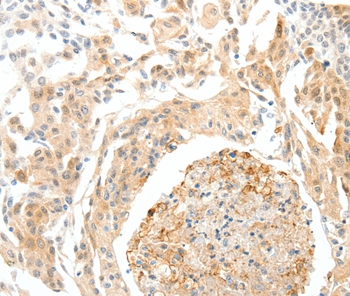

Immunohistochemical analysis of paraffin-embedded Human brain tissue using #37239 at dilution 1/50.

Immunohistochemical analysis of paraffin-embedded Human cervical cancer tissue using #37239 at dilution 1/50.